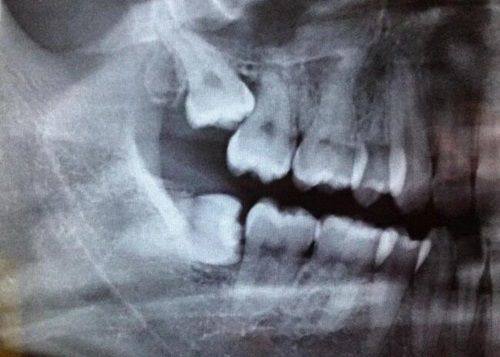

(一)郑州拜尔口腔医院种植牙价格表:

郑州拜尔口腔医院收费价格表种植牙多少钱?种植牙3980元起。这里要提醒大家,“元起”不是所有人都能拿到这个价哦!价格差异主要来自两方面:一是种植体品牌——国产、韩国、美国等品牌的工艺、材料成本不同,进口种植体的稳定性和寿命通常更好,价格也更高;二是个人口腔条件——如果牙槽骨骨量不足需要植骨粉,或者有重度牙周病要先治疗,这些额外步骤都会增加费用,所以具体价格得医生面诊评估后才能确定,别被“起价”误导啦。

(五)郑州拜尔口腔医院拔牙价格表:

4. 阻生智齿拔除价格:800元起/颗

郑州拜尔口腔医院收费价格表拔牙多少钱?拔牙50元起/颗。价格差距主要在“难度”上:儿童乳牙松动了一拔就掉,费用较低;成人松动牙也不难;但智齿就不一样了——如果是阻生智齿(埋在牙龈里),需要切开牙龈、去骨,甚至分根才能拔出来,耗时又费力,费用自然贵特别多。